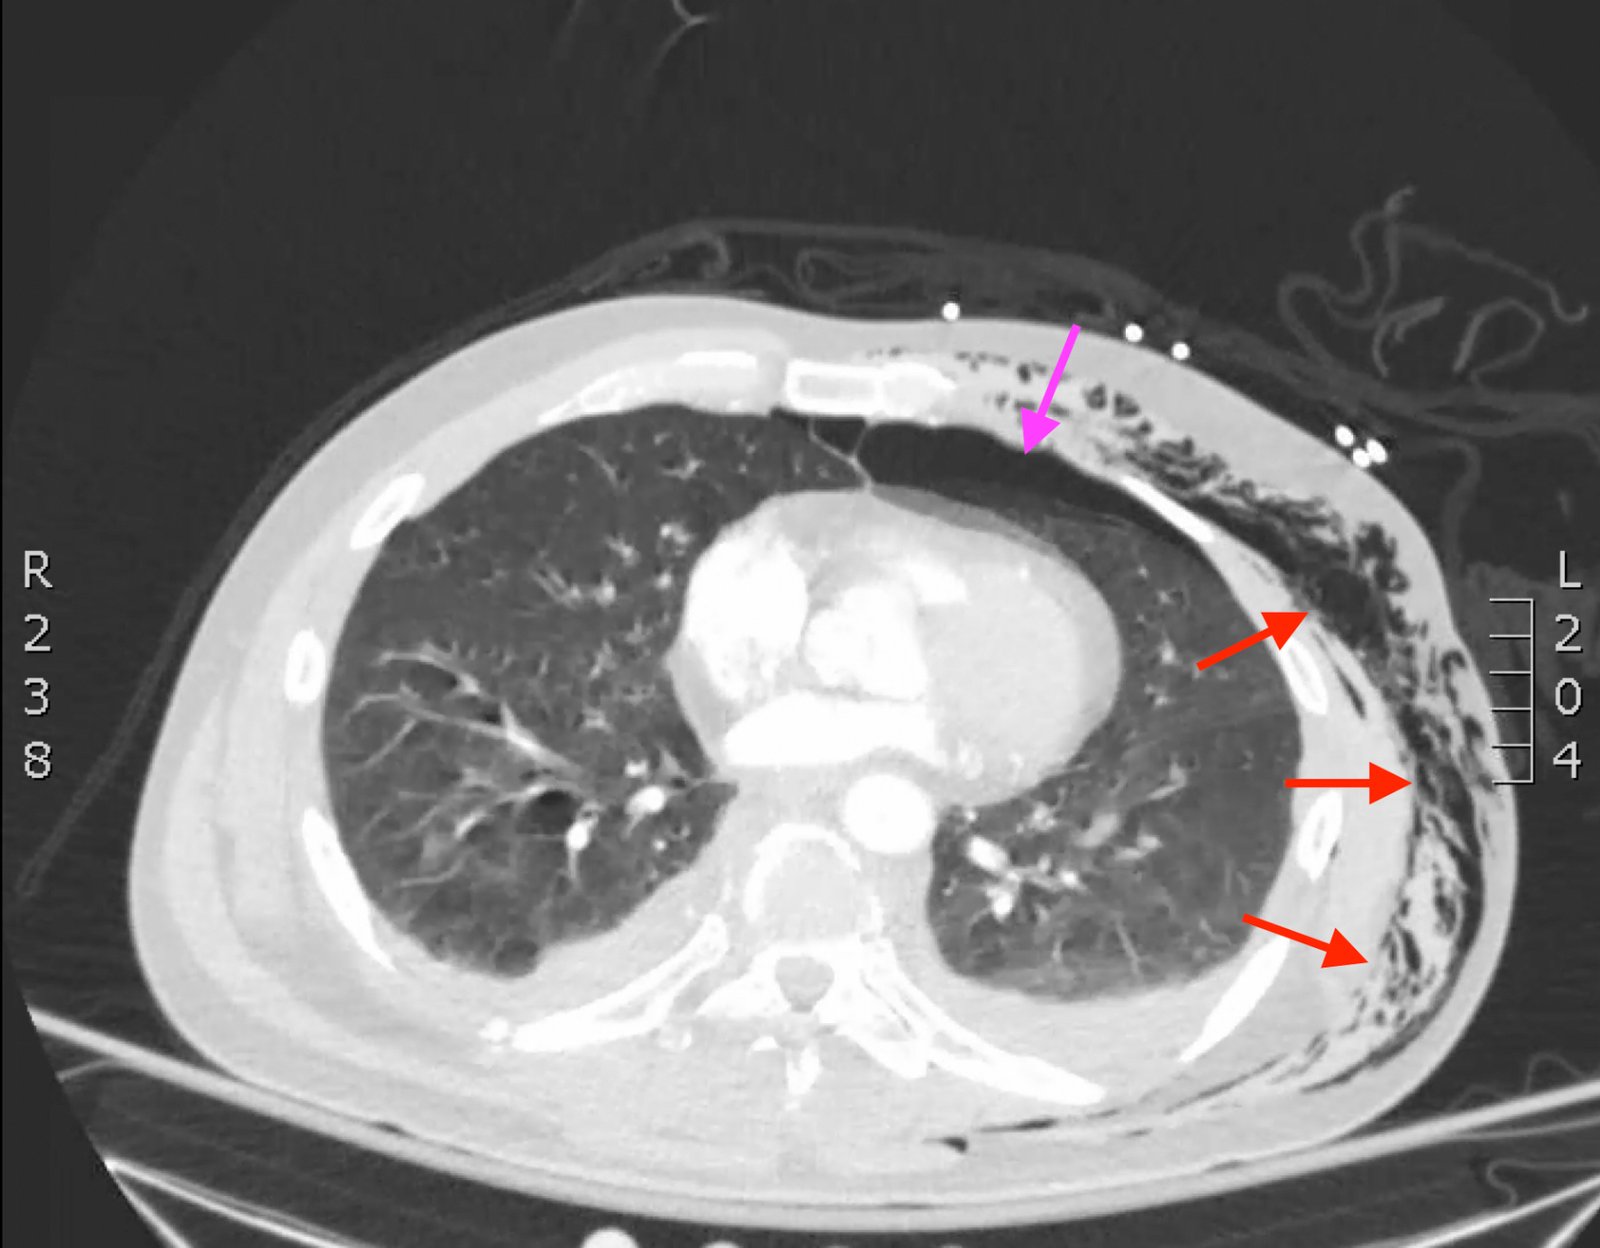

Plain film anteroposterior (AP) radiography of the chest shows left-sided subcutaneous emphysema (red arrow) with overlapping muscle striations of the pectoralis major (green arrow). After chest tube placement (blue arrow), AP chest radiography shows persistent left-sided subcutaneous emphysema (red arrow). CT of the chest shows pneumomediastinum (blue arrow), left apical pneumothorax (pink arrow), and subcutaneous emphysema (red arrow) at the level of T2. At the level of T6, rib fractures can be visualized on the CT (yellow arrow). At the level of T8, left sided pneumothorax is also seen (pink arrow) as the absence of lung tissue on CT.

Injuries of the thorax account for 25% of all mortality in trauma patients, of which many are preventable deaths by simple interventions.1,2 One sign commonly seen in patients with chest trauma is subcutaneous emphysema. The presence of this underlying emphysema has been suggested to be a sign of injury to the respiratory tract, making it clinically significant.3,4 Specifically, subcutaneous emphysema has been shown to be a clinical predictor of occult pneumothorax, with an odds ratio of 5.47.3 Furthermore, these injuries to the respiratory tract (pneumothorax /hemothorax, pneumomediastinum, etc.) can lead to hemodynamic instability and respiratory failure.4-6